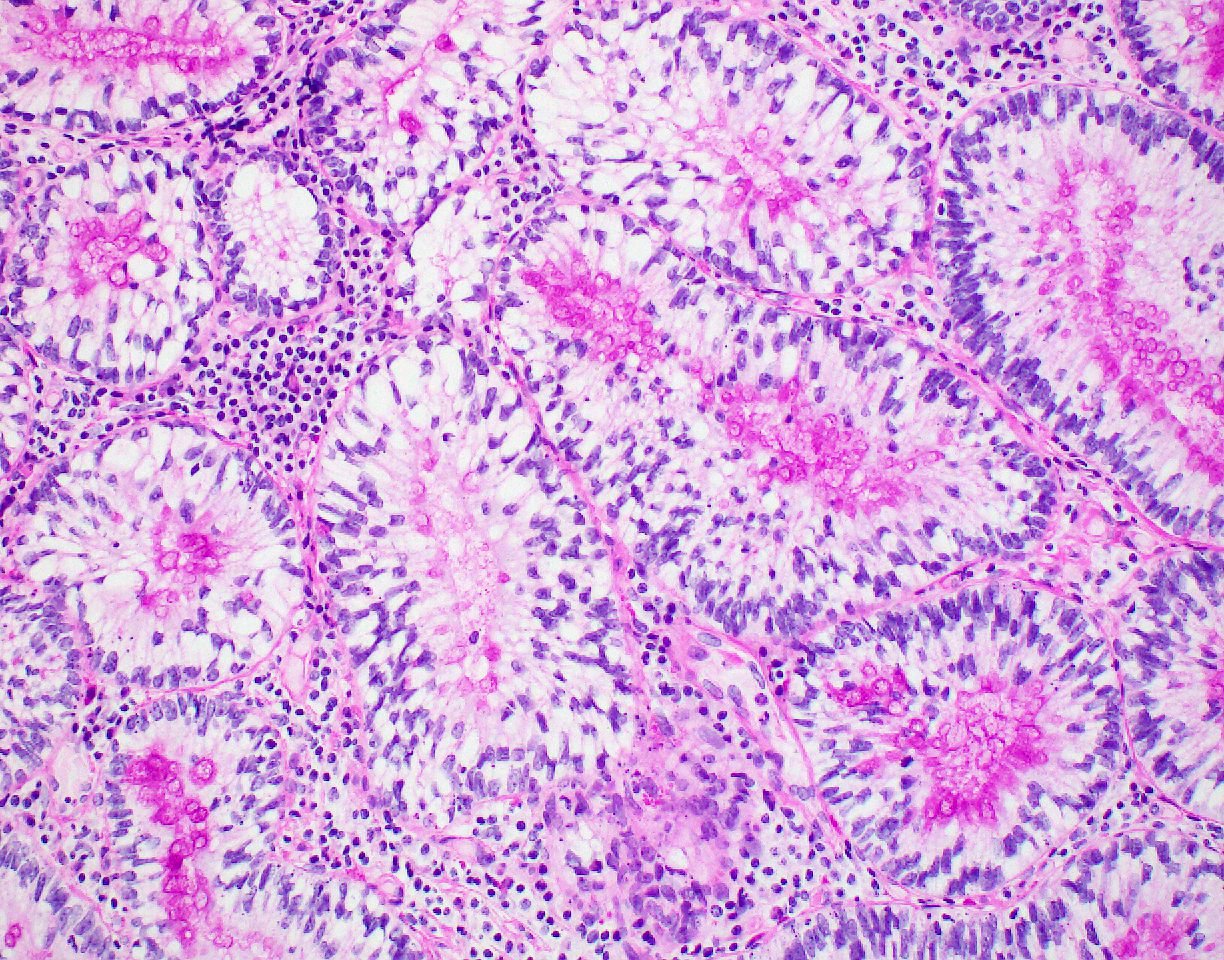

Microscopic (histologic) description

- Polypoid colonic mucosa covered with dysplastic epithelium comprised of hyperchromatic, elongated nuclei arranged in a pseudostratified manner

- Dysplasia is typically low grade but may also be high grade, with architectural (cribriforming, luminal necrosis) and cytologic changes (vesicular chromatin, nucleoli, loss of basal polarity)

- Abrupt transition from normal to dysplastic mucosa is commonly present

- Variable amounts of mucin loss

- Metaplasia may be present: osseous, squamous or Paneth cells (J Clin Pathol 2005;58:220, J Surg Oncol 1984;26:130)

- Pseudoinvasion can mimic progression to adenocarcinoma but displaced glands are benign and surrounded by lamina propria and often hemosiderin (Mod Pathol 2015;28:S88)

- May rarely show clear cell features (Am J Surg Pathol 2010;34:1344)

Microscopic (histologic) images

Contributed by Andrew L.J. Dunn, M.D. and Christopher Hartley, M.D.

Contributed by @Andrew_Fltv and @liverwei on Twitter